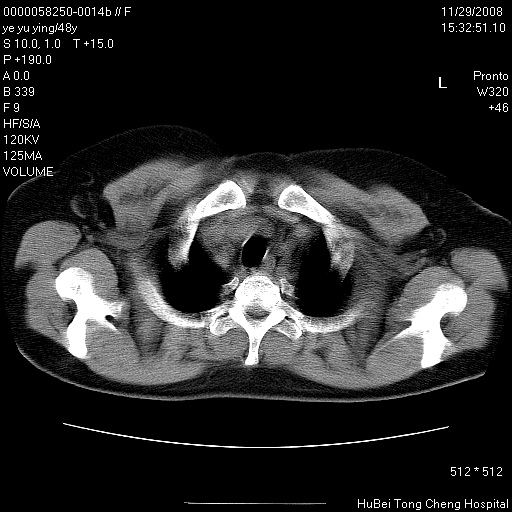

以下是引用zsl6918在2008-11-29 21:47:00的发言:[br]恶性肿瘤病史,转移瘤首先考虑。脂肪肝,胆囊结石。

以下是引用liuyue在2008-11-30 5:44:00的发言:[br]1.左肺病变,首先考虑感染性病变,转移待排;建议治疗后复查。[br]2.肝脏密度普遍减低,考虑与化疗有关。[br]3.胆囊结石.